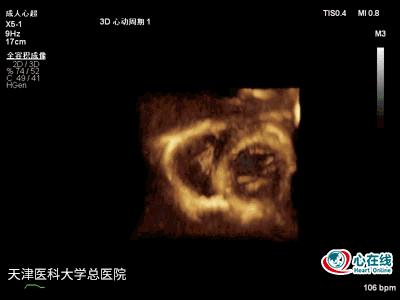

图5. 三维心尖四腔心切面示右心室内可见活动度小的巨大不规则中等回声团块。

图6. 三维胸骨旁左心室短轴切面示右心室内可见活动度小的巨大不规则中等回声团块。